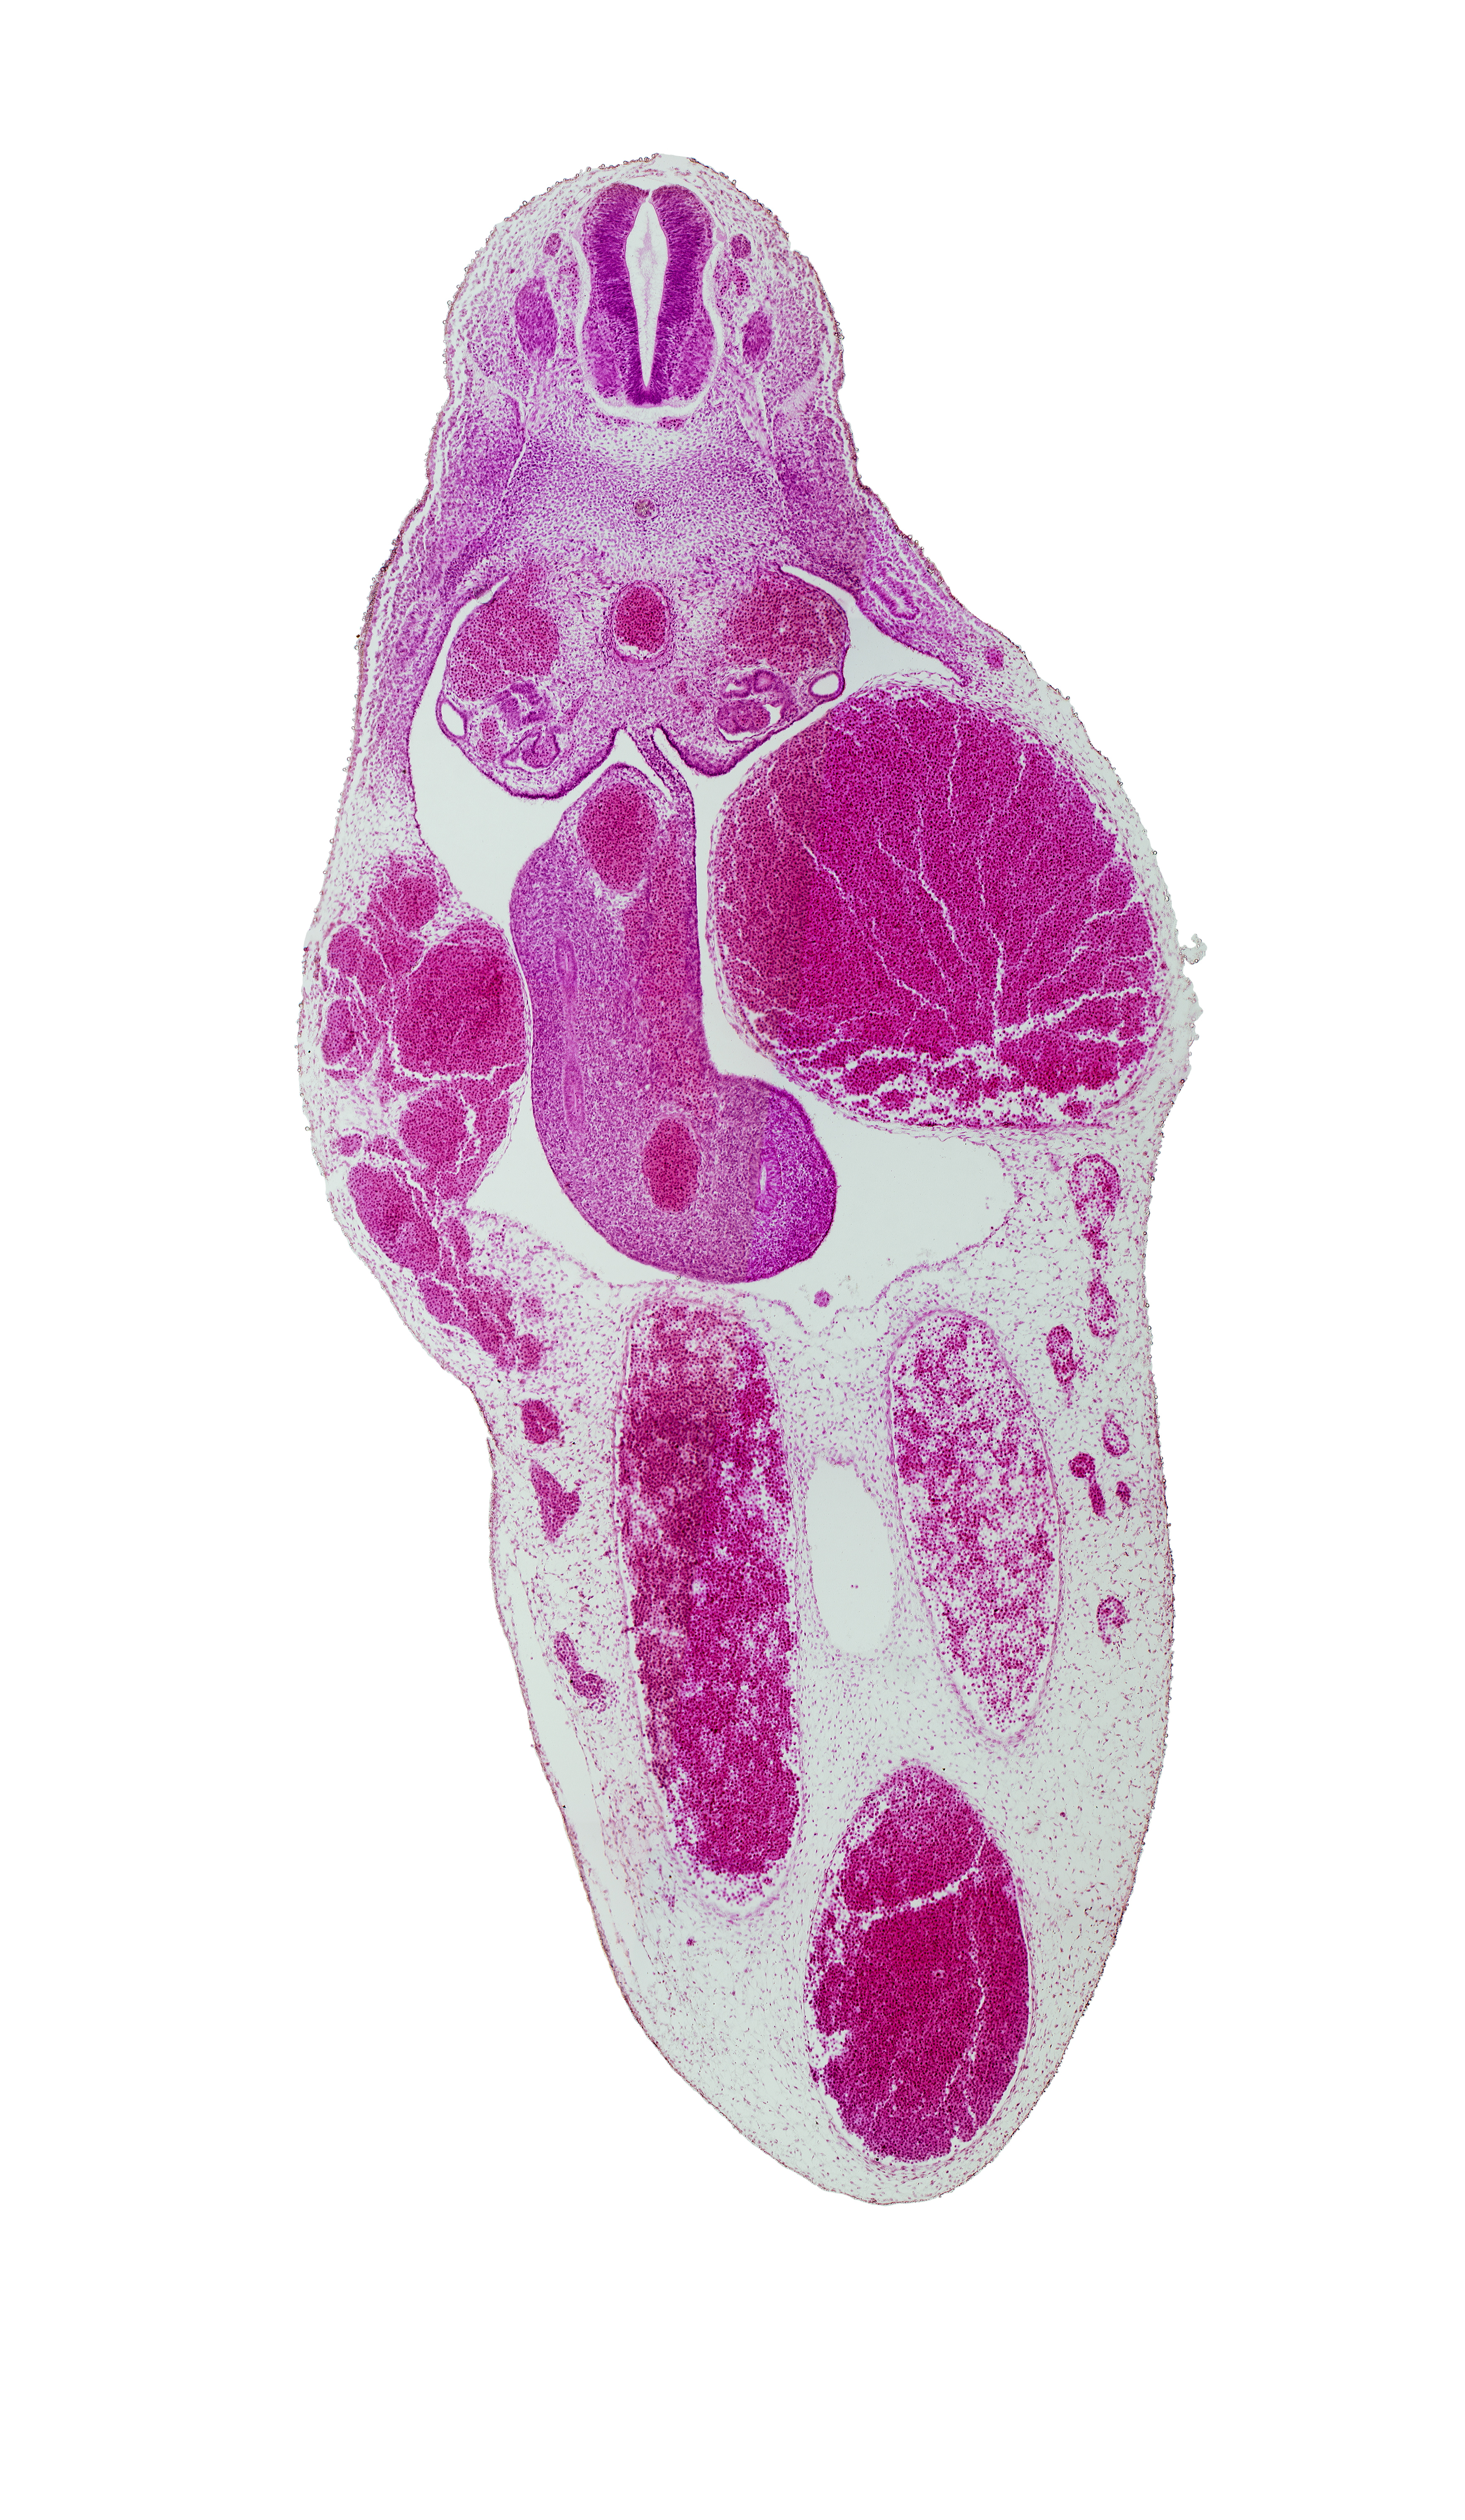

T-8 spinal ganglion, allantois, aorta, central canal, floor plate, gonadal epithelium, left umbilical artery, mesentery, mesonephric duct, midgut, notochord, right umbilical artery, roof plate, superior mesenteric artery, umbilical vein

Keywords: T-8 spinal ganglion, allantois, aorta, central canal, floor plate, gonadal epithelium, left umbilical artery, mesentery, mesonephric duct, midgut, notochord, right umbilical artery, roof plate, superior mesenteric artery, umbilical vein